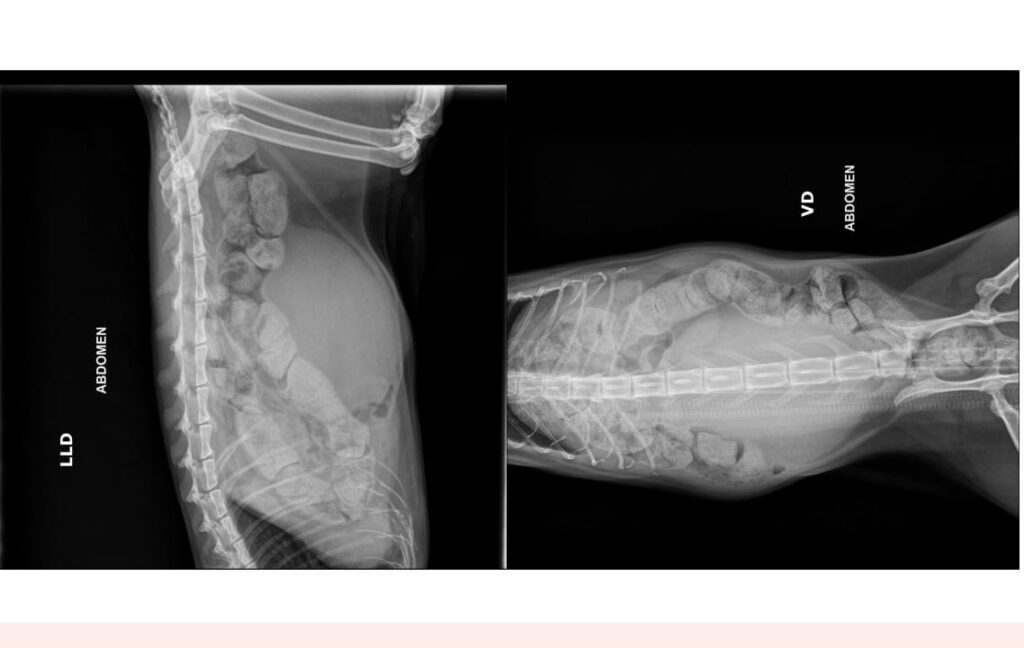

“Primeiramente, eu e todos os médicos veterinários envolvidos no caso estamos profundamente tristes com a morte de Lucy. Entretanto, as imagens radiográficas e os exames complementares realizados no animal demonstram um fecaloma (acúmulo grave de fezes secas e resistentes no intestino, dificultando ou impedindo a defecação, e que pode ser fatal se não for tratada) e um bexigoma (emergência veterinária causada pelo acúmulo de urina na bexiga devido a uma obstrução ou problema neurológico)”, afirma o médico veterinário.

“Os meus colegas médicos veterinários sabem que um quadro de fecaloma de colo descendente, transverso e ascendente, megacólon e bexigoma não surgem em menos de 24 horas”, complementa Vicente.